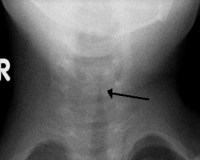

J38.6 Стеноз гортани